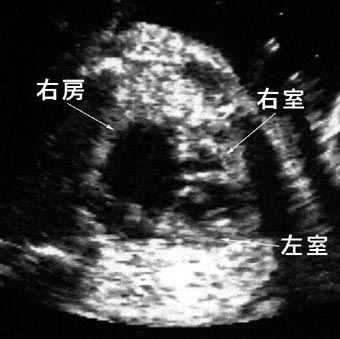

左心低形成症候群

右房と右室は拡大しているが、左室は筋組織のみで内腔を認めない。